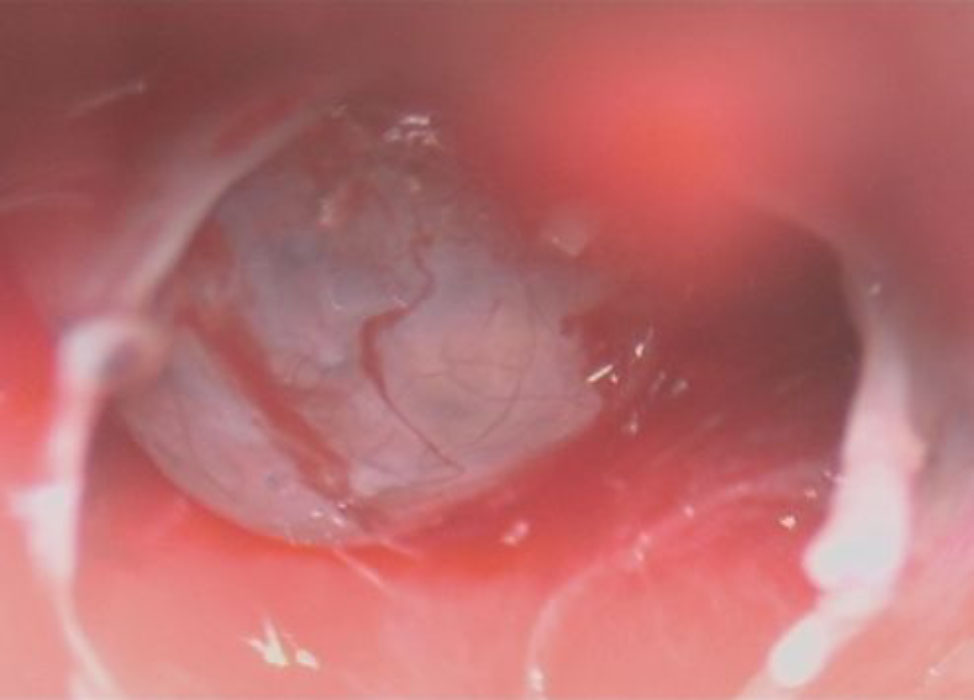

摘出 前

摘出 中